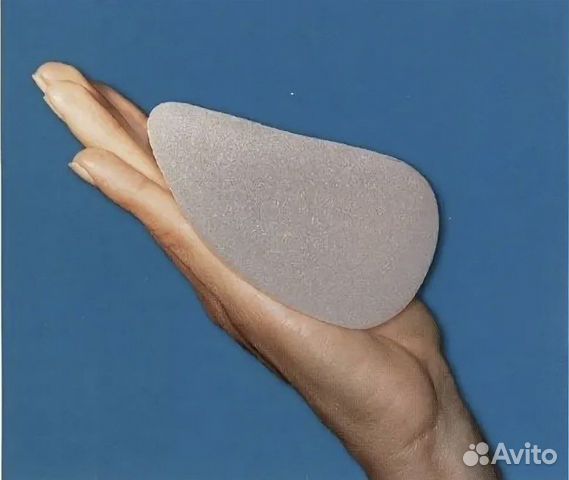

Анатомические импланты Eurosilicone

Раздел: Визуальный дайджест